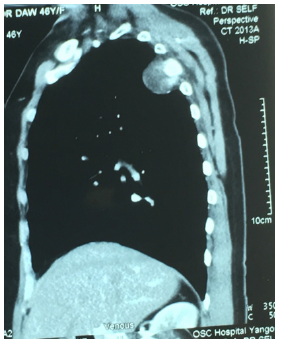

Urine examination was normal. LE cell was negative, Extractable nuclear antigen profile was negative. Serum creatinine and blood urea were normal. Ultrasound abdomen was normal. Chest radiograph showed an ill- defined mass, 3cm in largest diameter at right apical area with erosion of the 4th rib. It is shown in Figure 1. It became larger over 1year as demonstrated in Figure 2. CT scan chest revealed a mass at posteromedial site with the 4th rib erosion Figures 3,4. The other investigations were as follows: hemoglobin 12g%; total WBC count 6.2X109/L; platelets normal. Liver function tests were normal. Lung function test showed normal FEV1; normal FEV1 and FVC ratio. The cholesterol was raised. Her blood group was B Rh negative (Figure 1-4).

Haemangioma is a benign vascular tumor; it rarely affects the ribs. This patient had erosion in 4th rib. This is another reason for writing this case. Majority of the patients with hemangioma presented with solitary lung nodule, while 5 patients showed multifocal lesions [19]. One study evaluated the CT and PET-CT features of Solitary Pulmonary Capillary Hemangioma (SPCH) with clinicopathologic correlations. And, they found that SPCH was often incidentally detected in young and middle-aged adults, commonly as an ill-defined part-solid nodule with air bronchogram, perivascular lucency, and fluctuation in size or density on CT and hypometabolism on PET-CT [20,21]. In this case, SPN was situated at right apex; posteromedial lesion. Haseli et al discussed the role of imaging and its strengths and limitations for diagnosing posteromedial chest wall lesions [22].